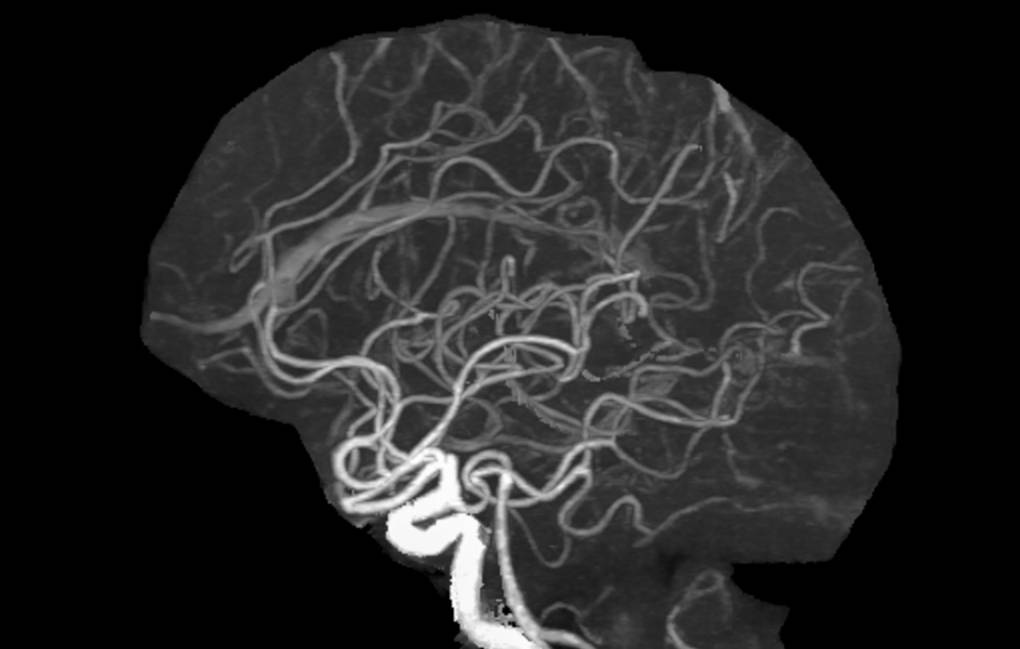

"Новая методика позволяет автоматически реконструировать сосудистое дерево пациента и рассчитывать морфологические параметры для точной детекции областей патологического сужения сосудов. Основной целью исследования является создание эффективного инструмента для автоматической идентификации стенозов церебральных артерий на трехмерных КТА-изображениях", - отметили в пресс-службе.

Тестирование алгоритма на выборке из 118 КТА-серий показало высокую точность детекции стенозов - 83,1%. Также сделана трехмерная визуализация реконструированного сосудистого дерева с указанием локализации выявленных патологических сужений. Внедрение алгоритма в клиническую практику позволит значительно ускорить и упростить процесс диагностики стенозов интракраниальных артерий.